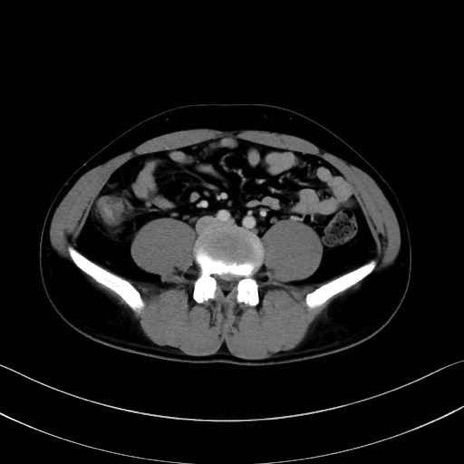

4. 深層外旋六筋(股関節の深部)

梨状筋 (Piriformis)

内閉鎖筋 (Obturator internus)

外閉鎖筋 (Obturator externus)

大腿方形筋 (Quadratus femoris)